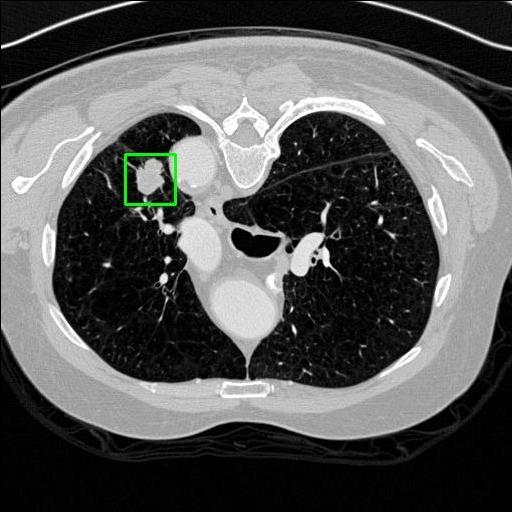

We developed an AI-based system using deep learning models for analyzing lung CT scans to detect and classify pulmonary nodules. We chose the YOLOv11 architecture for its enhanced object detection capability and adapted it specifically for medical imaging, incorporating pixel-level precision and severity classification.

Classification into three severity levels with colored bounding boxes.

Designed a severity classification system that categorizes nodules into null, moderate, and severe using colored bounding boxes, assisting in rapid clinical decision-making.